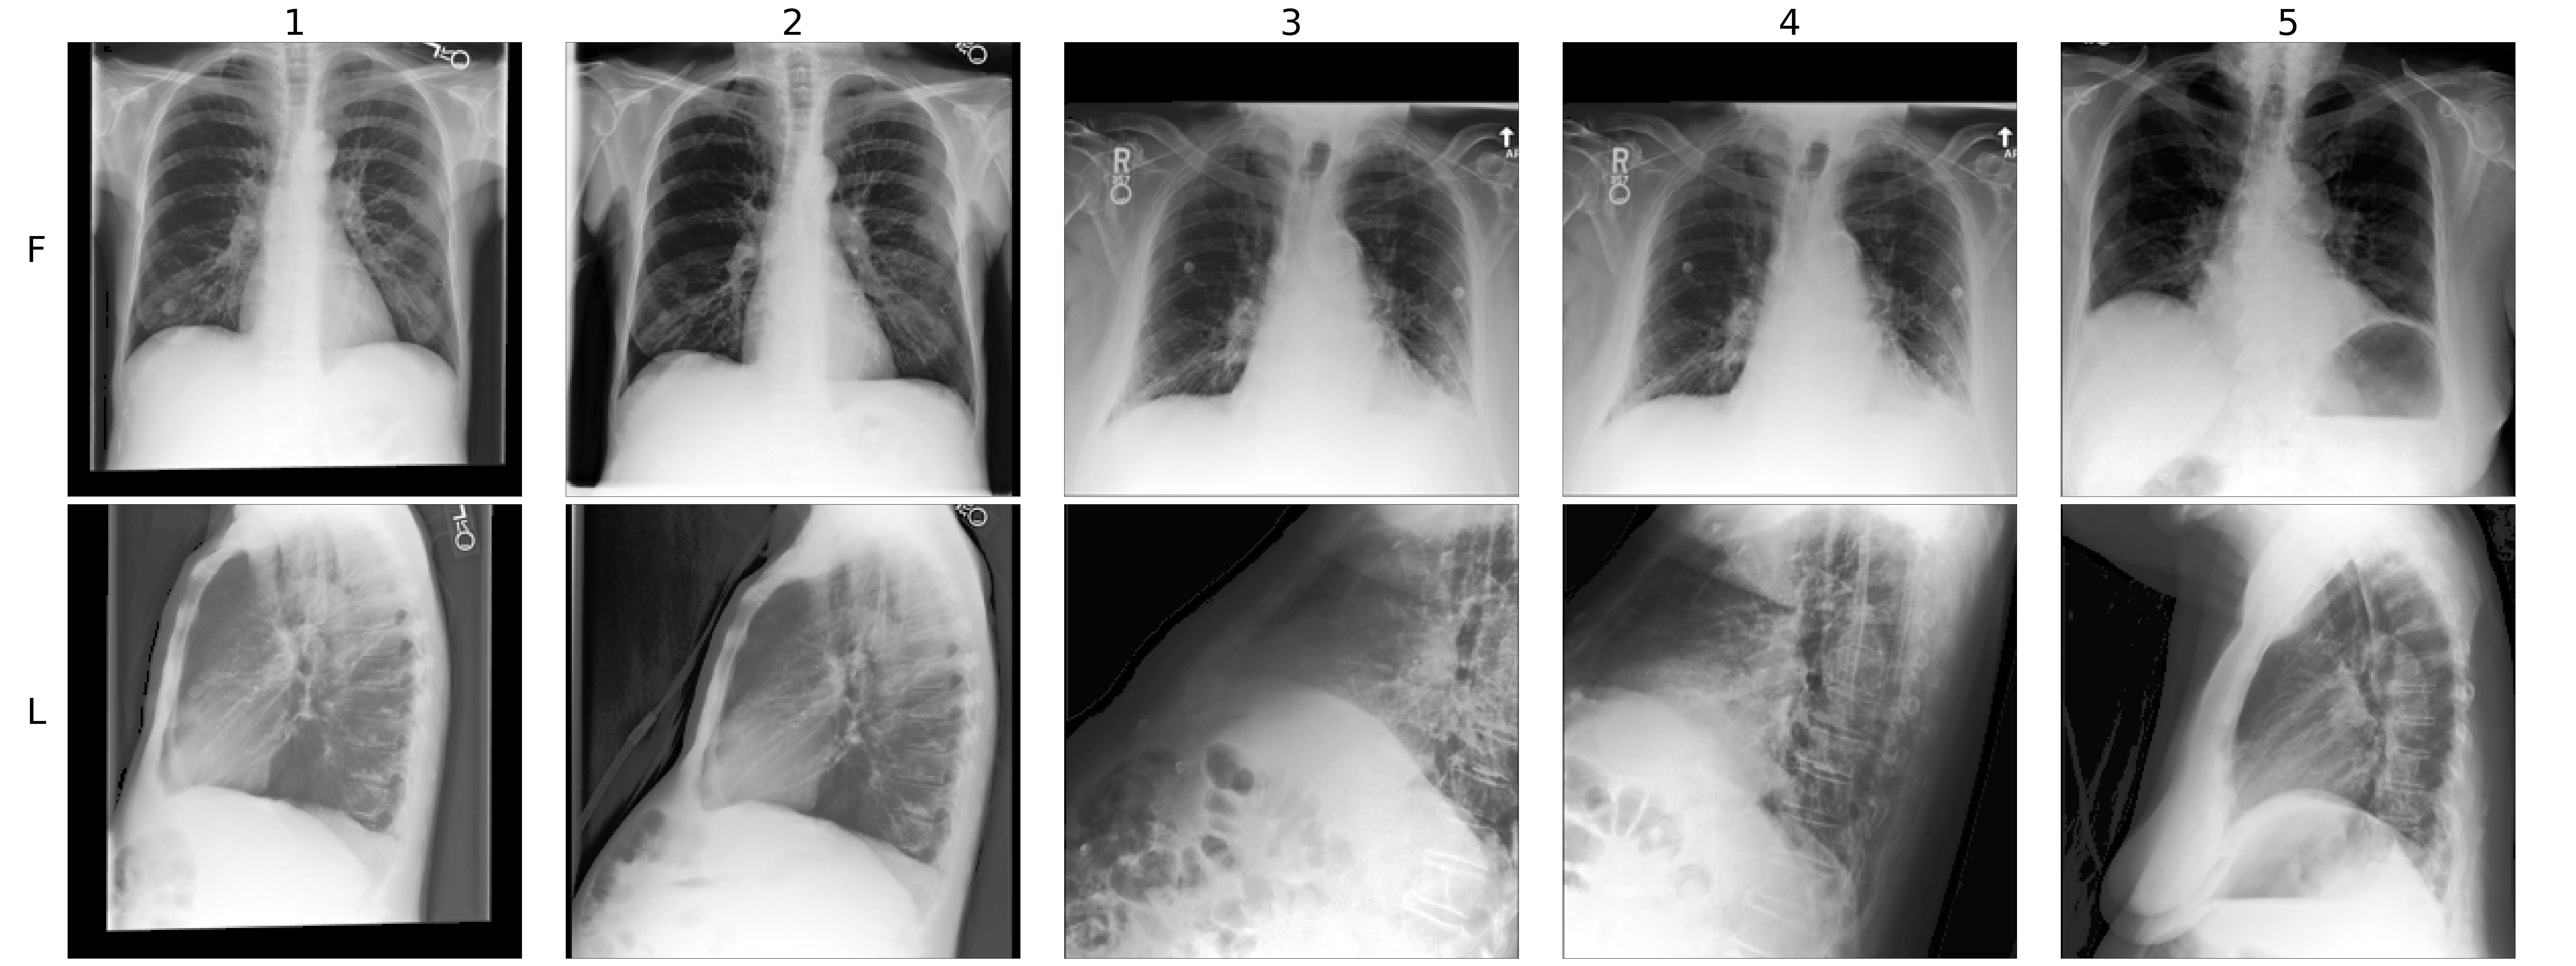

In this work, we consider frontal and lateral view positions as two distinct modalities, i.e., . Further details on data preprocessing, dataset splitting, and examples of these bimodal tuples are provided in Appendix 2.

Appendix A Dataset

The dataset we use in our experiment is a multimodal interpretation of the original MIMIC-CXR dataset. The original MIMIC-CXR dataset (Johnson et al., 2019b) comprises high-resolution chest X-ray images related to imaging studies. A study may include multiple chest X-ray images captured from several view positions. We categorized these views into two primary modalities: frontal (including “AP” and “PA” views) and lateral (including “LL” and “Lateral” views). For each study, we pair every frontal image with every lateral image in all possible combinations. Studies lacking at least one frontal and one lateral image are excluded. This approach formalizes a new dataset composed of image pairs, thus offering a bimodal interpretation of the original MIMIC-CXR dataset. More rigorously, we define a dataset where each is a bimodal tuple composed of one frontal image and one lateral image of the same study. An image may appear in multiple tuples, but we ensure that each tuple is unique by having at least one different image. Examples of these bimodal tuples are illustrated in Figure 2.